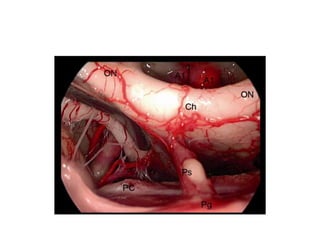

Endoscopic view of the anterior part of the Left Suprasellar area [ = Sub-

Chiasmatic Cisttern ] . A1 first segment of the anterior cerebral artery, AChA

anterior choroidal artery, GR gyrus rectus, ICA internal carotid artery, OC optic chiasm,

ON optic nerve, OT optic tract, PCoA posterior communicating artery, PG pituitary

gland, PitS pituitary stalk, MB midbrain, U uncus